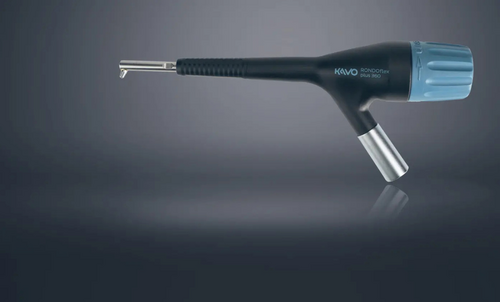

Fig. 5a, 5b e 5c

Mediante le stesse strip abrasive FitStrip, di diversa grana, l’odontoiatra sarà agevolato notevolmente senza dover ricorrere all’uso della fresa in determinati momenti della preparazione minimale.